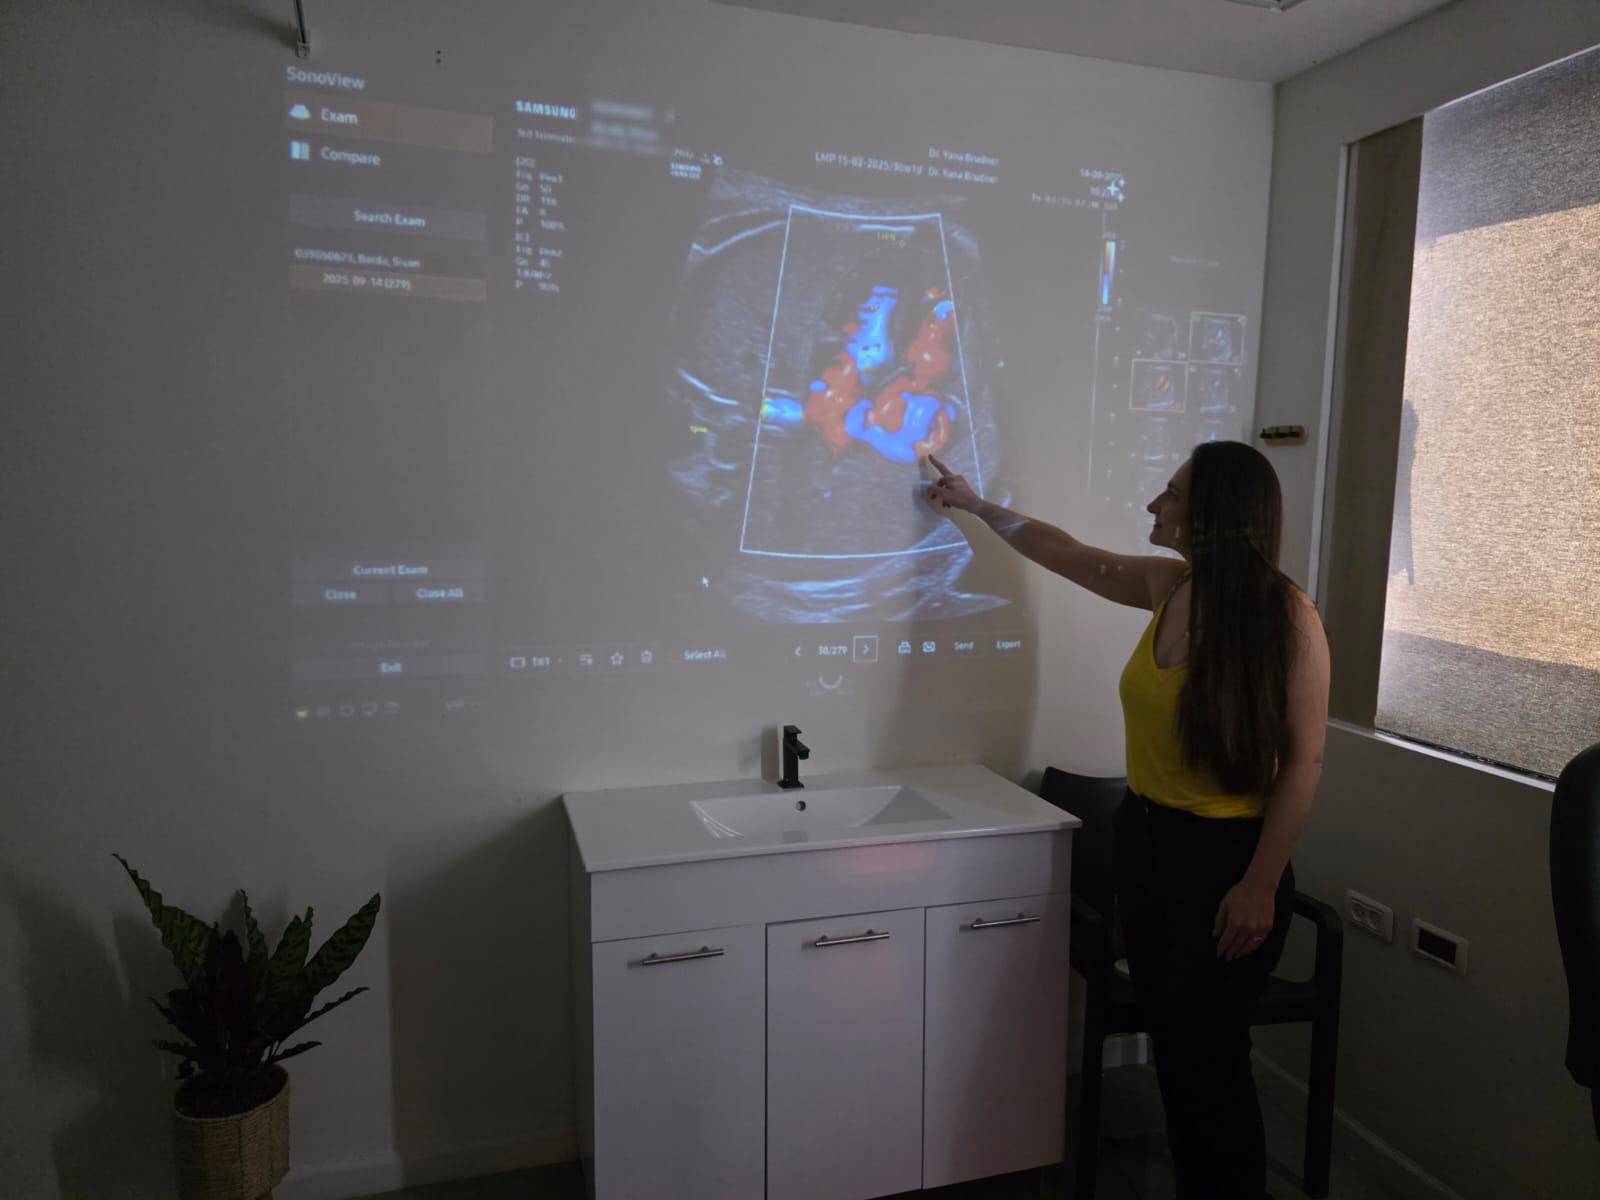

בדיקה זו מבוצעת בשליש השלישי של ההיריון, ומטרתה להעריך את מצבו העכשווי של העובר.

הסקירה כוללת בין היתר: מצג העובר, הערכת הגדילה, כמות מי השפיר, מיקום השליה וכן מבט חוזר על איברים עובריים.

מטרת הבדיקה היא לאתר מומים שמתפתחים או מתבטאים רק בשלבים המאוחרים של ההיריון.

הבדיקה מבוצעת לרוב בגישה בטנית, אך לעיתים נדרשת גם גישה נרתיקית, בעיקר במצבים בהם העובר במצג ראש – לשם הדמיה מדויקת יותר של המוח.